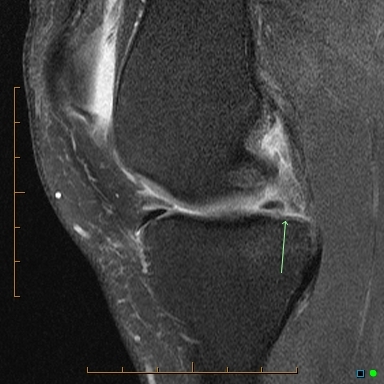

Meniscal root tear

Tear at the junction of the posterior horn medial meniscus and its attachment of the tibial eminence. This is known as the meniscal root.

Case Discussion

These tears are unusual and occur either as an acute injury in young patients or as a degenerative process in older patients. As the meniscus is reasonably well vascularised at the root, surgical repair is recommended in younger patients. In older patients with degeneration there is often associated chondral damage thus repair is more problematic and can fail.

Meniscal root tears are a type of meniscal tear in the knee where the tear extends to either the anterior or posterior meniscal root attachment to the central tibial plateau. They often tend to be radial tears extending into the meniscal root.

Radiographic features

MRI

Best assessed on T2 weighted sequences. When it involves the posterior root, medial root tears are easier to diagnose than lateral root tears.

On medial posterior root tears there is often 2:

shortening or absence of the root on sagittal images

vertical fluid cleft on coronal fluid-sensitive (T2) images

On posterior root radial tears of the lateral meniscus, the appearance may be similar to radial tears in other locations.

For root tears in general, sagittal imaging may demonstrate a meniscal ghost sign.

Other features include:

truncation sign on coronal images 4

features meniscal extrusion on coronal plane 4